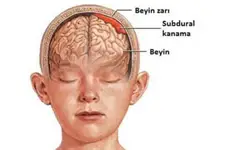

Bebeklerde beyin kistleri, genellikle doğumdan önce veya doğum sırasında oluşabilen sıvı dolu keseciklerdir. Bu kistler, beyin dokusunda veya çevresinde yer alabilir ve çoğu zaman zararsızdır. Ancak bazı durumlarda, beyin kistleri beyin fonksiyonlarını etkileyebilir ve tedavi gerektirebilir. Bu makalede, bebeklerde beyin kistlerinin belirtileri, tanısı ve tedavi yöntemleri hakkında detaylı bilgi verilecektir. Bebeklerde Beyinde Kist Belirtileri Bebeklerde beyin kistlerinin belirtileri genellikle kistin boyutuna, konumuna ve etkilerine bağlıdır. Belirtiler şunları içerebilir:

Bu belirtiler, kistin beyin üzerindeki etkilerine bağlı olarak değişiklik gösterebilir. Dolayısıyla, ebeveynlerin bebeklerinde bu tür belirtiler gözlemlemesi durumunda hızlı bir tıbbi yardım alması önemlidir. Bebeklerde Beyin Kistlerinin Tanısı Bebeklerde beyin kistlerinin tanısı genellikle aşağıdaki yöntemlerle yapılır:

Bu tanı süreçleri, doktorun kistin doğasını anlamasına ve uygun tedavi yöntemini belirlemesine yardımcı olur. Bebeklerde Beyin Kistlerinin Tedavisi Bebeklerde beyin kistlerinin tedavisi, kistin türüne, boyutuna ve bebeğin genel sağlık durumuna bağlı olarak değişiklik göstermektedir. Tedavi seçenekleri şunlardır: